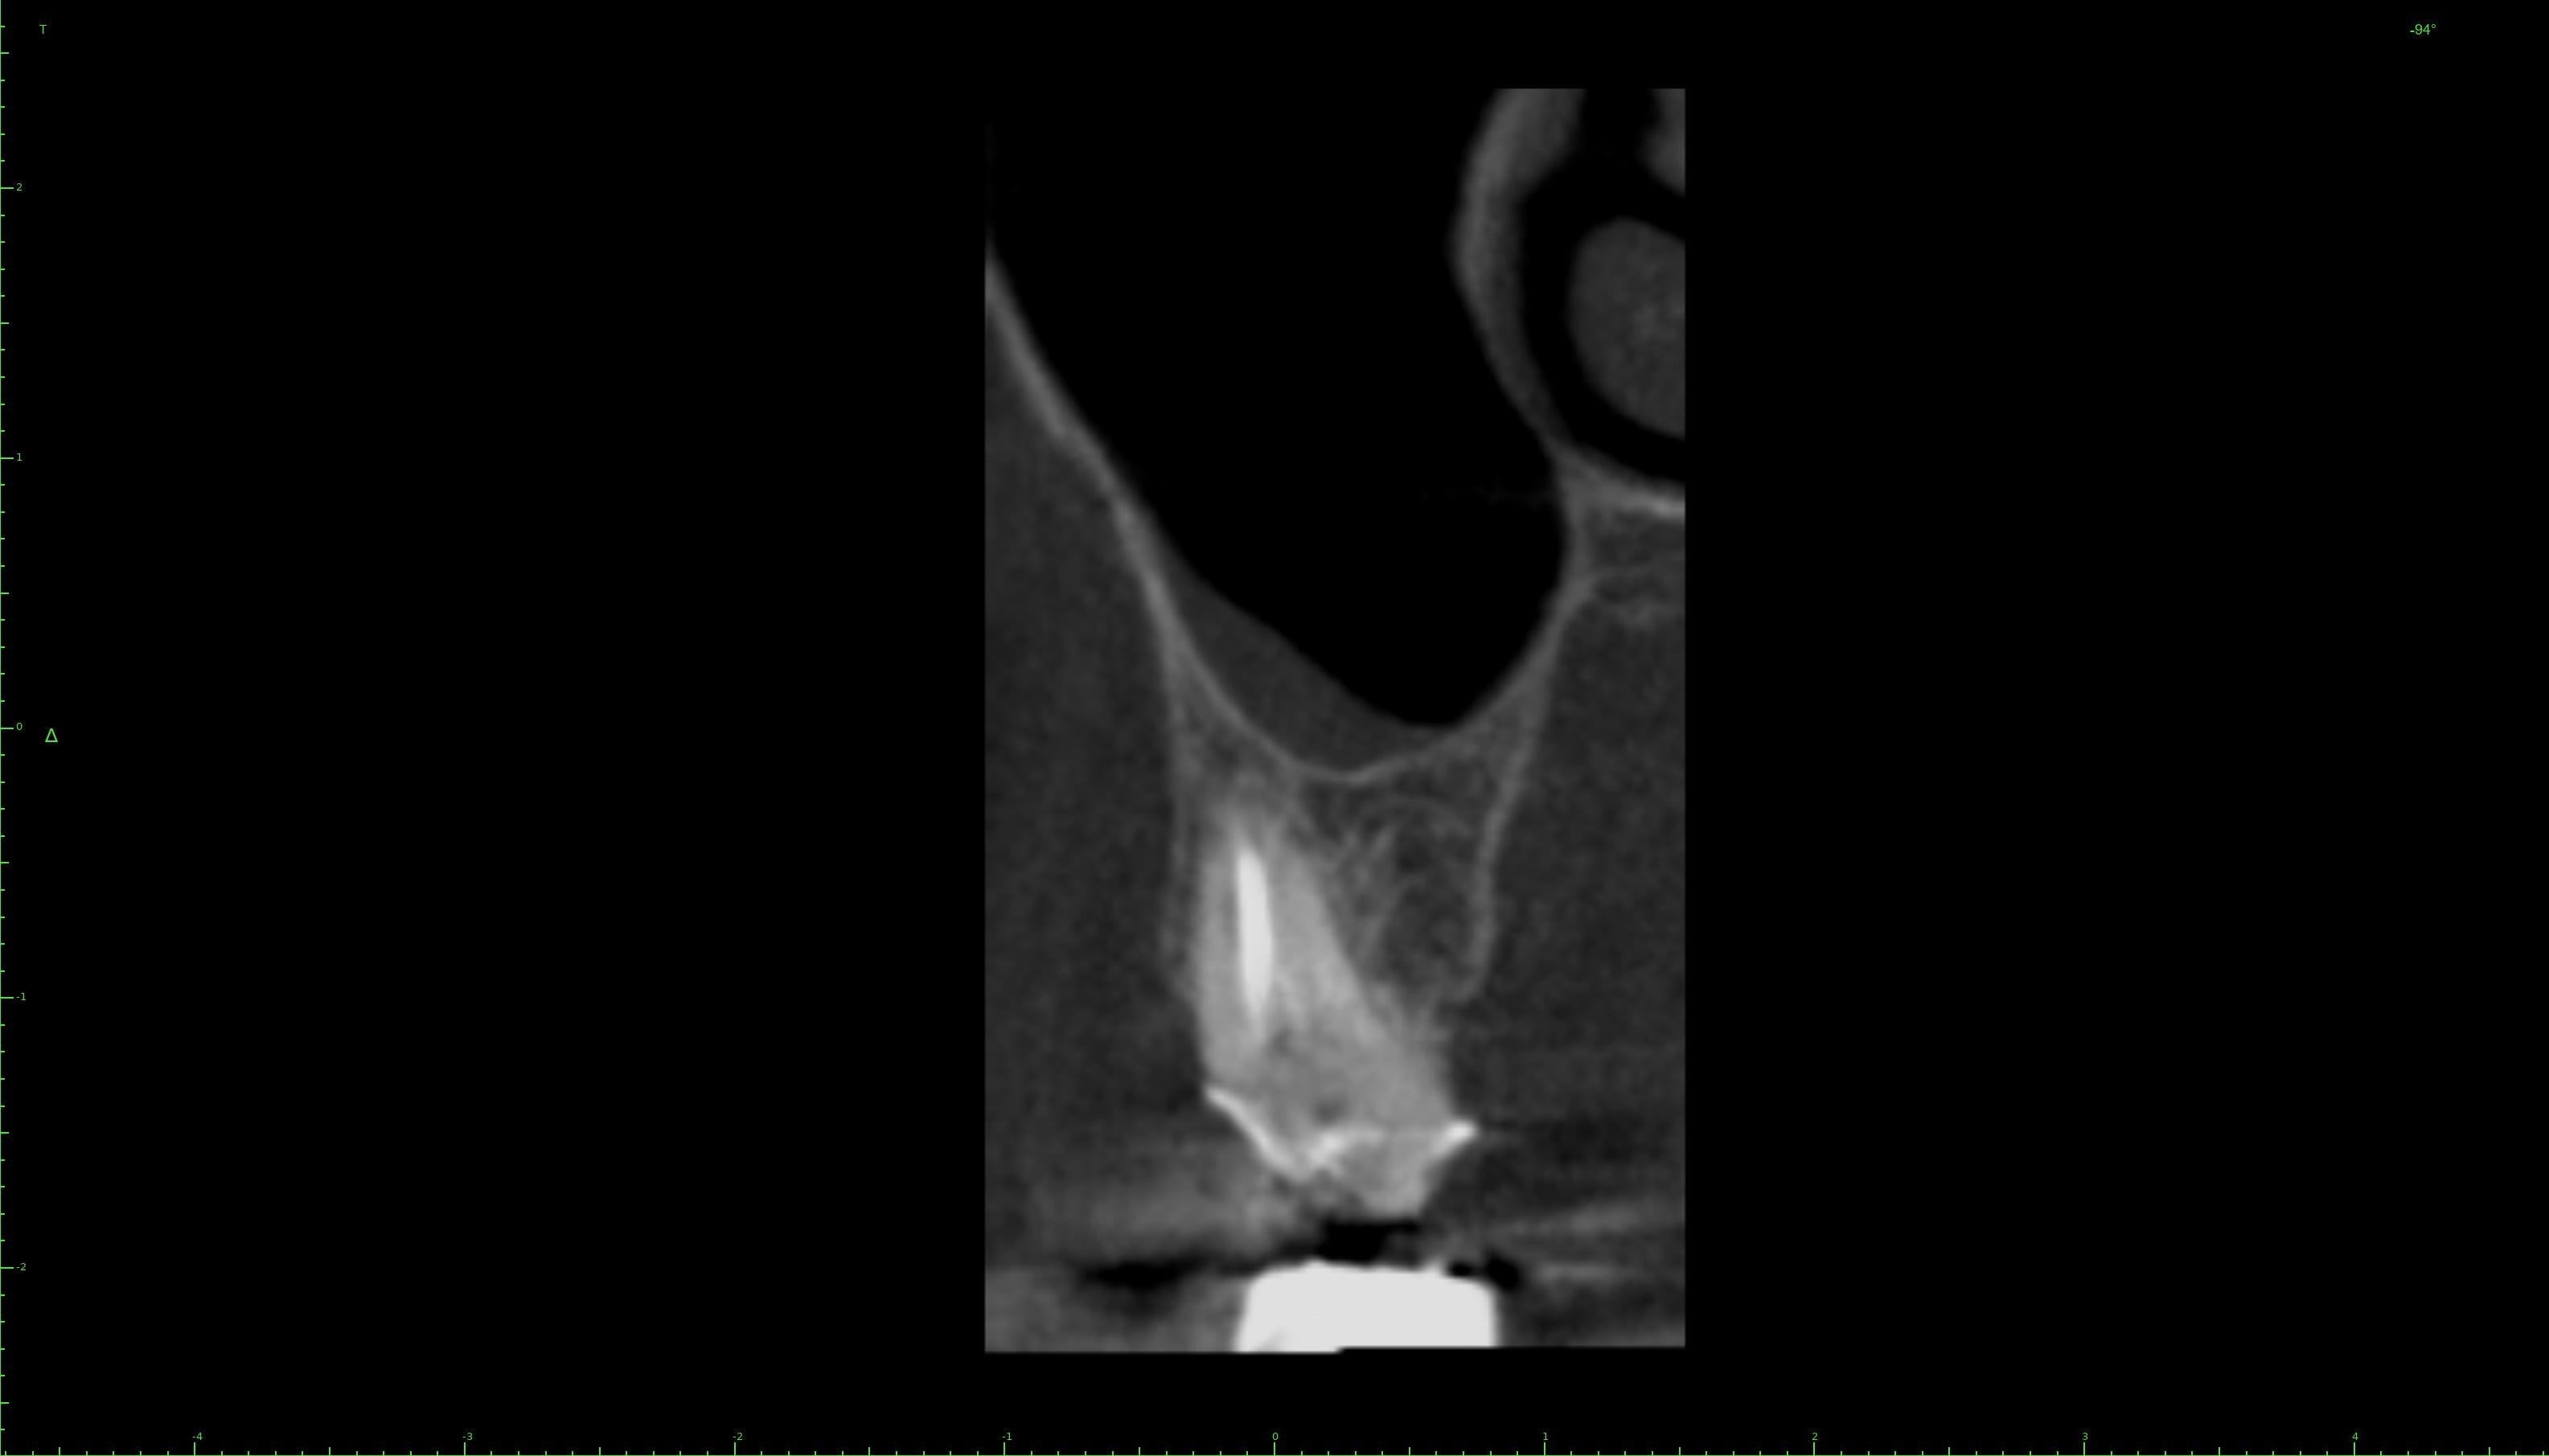

J'ai fait un conebeam de la 26.

L'obturation des racines est correcte, il y a juste une petite image apicale au niveau de la racine palatine avec un léger dépassement de pâte.

Pas de coupes horizontales ?

Le MV2 non obturé ici peut parfois, selon sa configuration, causer des douleurs variées.

Je peux me tromper, les coupes ne sont pas idéales pour conclure ☝️

Pour répondre à Dentarue: je viens de faire des coupes horizontale et centrées sur la racine vestibulaire en tournant autour d'un potentiel MV2. La gutta et le ciment font un joli artefact radio donc ce n'est pas concluant.

On le voit très bien sur ta 3d.

Aucune gloire, on ne voit que ça.

Chercher une deuxième entrée en vestibulaire quand on voit sur cette coupe et sur la coupe horizontale que c’est le palatin qui n’est pas obturé, … les mots me manquent.

Il cherche en vestibulaire de MV mais c’est en palatin de MV qu’il fallait chercher, cela me semblait aller sans dire ☝️

Tout est sur la 3d.

Le MV2 n’est pas très proche de la furcation mais plutôt plus mésial que le MV1. Il est très visible à la radio et ne doit pas être bien compliqué à traiter, mais pour ça il faut s’en donner les moyens et ça commence par la digue.

Tu nous dis qu’il n’y a pas de MV2 et tu nous montres des coupes où il saute aux yeux puis tu vois la patiente entre deux pour désobturer MV1 sans digue… et laisser MV2 non traité…

Il est plus mésial.

Si ce qu’on voit est le MV1 désobturé, le MV2 est à peu de chose près là où est ta flèche verte. Son entrée est souvent plus apicale. Le trouver est une chose, le négocier une autre, souvent bien chronophage.